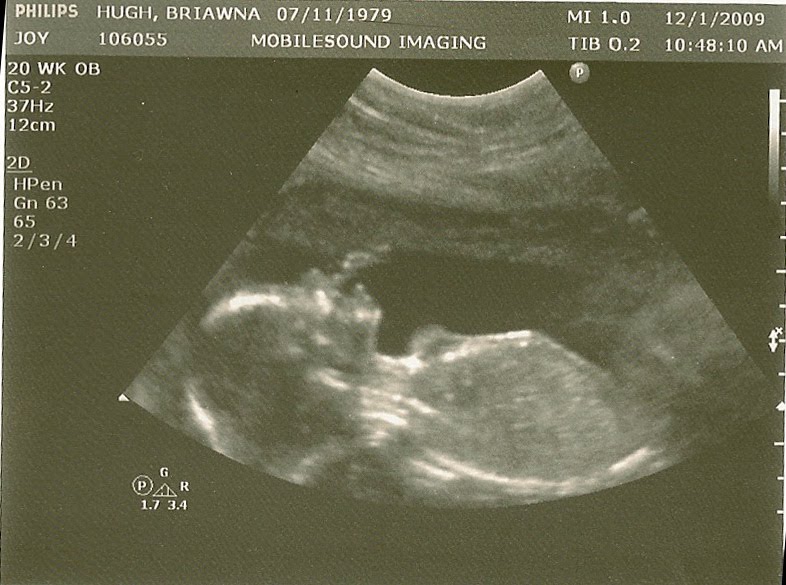

BABY! Are you surprised? I love seeing people's reaction when we tell them we're not finding out the gender of our baby. There are lots of logical reasons why being surprised by this one makes sense (we're prepared for either one, we're moving shortly after the baby's born so no need to set up a nursery, etc.) but really it's just because I've always wanted to be surprised. I'm very proud of the fact that neither Ronell or I had the urge to find out while at our ultrasound today. All that really mattered to me was making sure our little one is healthy. And everything was perfect, even down to the little one sucking a thumb while the technician snapped this shot.